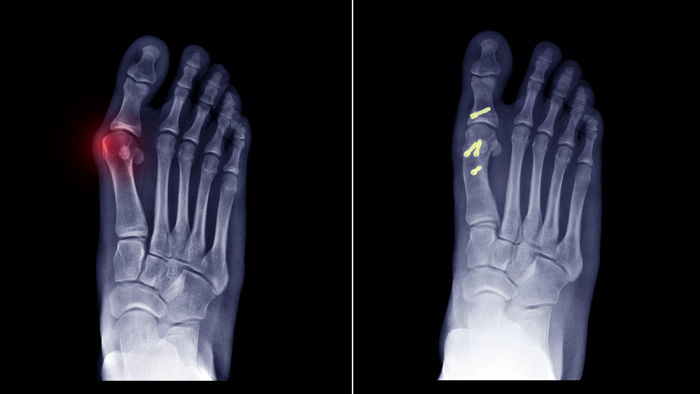

- Bunion: In this deformity, the base of your first toe swells up and protrudes. It can push against your second toe and overlap the third.

- Surgery: Unless the deformity significantly affects the quality of your life, surgery will not be recommended. If your deformity causes pain and discomfort, there are surgical procedures that can help alleviate the condition. Some procedures include synovectomy (removal of the synovium), joint replacement, joint fusion and bunion surgery. It is important to note that while surgery can fix the deformity, it cannot cure the underlying cause, especially if it is rheumatoid arthritis or osteoarthritis.